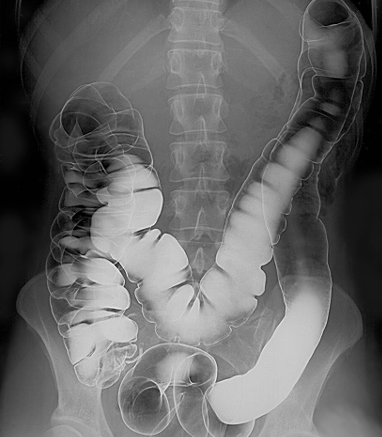

Intestinal tract barium enema

© Glitzy queen00 at English Wikipedia., Public domain, via Wikimedia Commons

By Glitzy queen00 at English Wikipedia., Public domain, via Wikimedia Commons